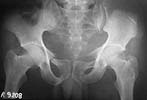

On admission patient was hypotensive. Evaluation revealed him to be having an unstable pelvic ring injury, D12 vertebral body fracture, free fluid in the abdomen and a suspected urinary bladder injury. After his haemodynamic status was better he was taken up for an emergency laparotomy (midline approach). Though there was free blood stained fluid in the peritoneum no hollow viscus injury or other organ damage was noted. Urinary bladder contusion present but no tear. At he same sitting the anterior pelvic ring was stabilised using reconstruction plates through an extended Pfannensteil approach. After a couple of days the posterior ring was stabilised using reconstruction plates (posterior approach). The spine was not interfered surgically since this was inherently stable and there were no neurological findings. The posterior wound grumbled for some time and settled down. He was kept in bed but allowed free turning in bed.

The X rays and few CT reconstructions attached. Kindly give your valuable comments. What all would have been better ways of management?